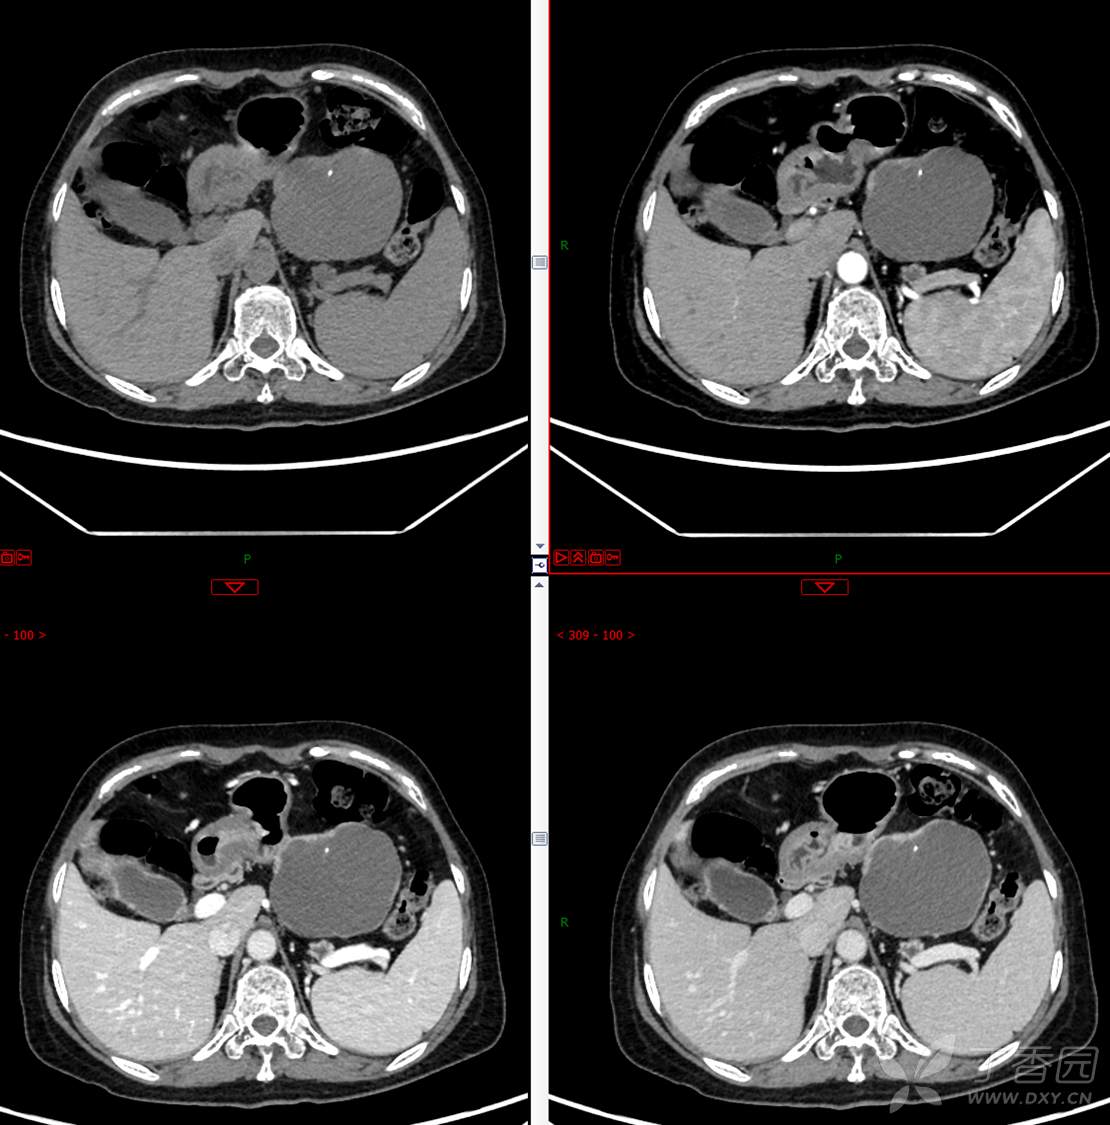

中老年女性胰腺占位,“奶奶瘤”or“妈妈瘤”?请分析领丁当!

主 诉:发现胰腺占位性病变3月

现病史:患者3月前就诊于**市人民医院行腹部增强CT发现胰尾占位性病变,无腹痛、腹胀,无恶心呕吐,无黄疸,无呕血黑便,无胸闷憋气,无寒战高热,未行特殊治疗